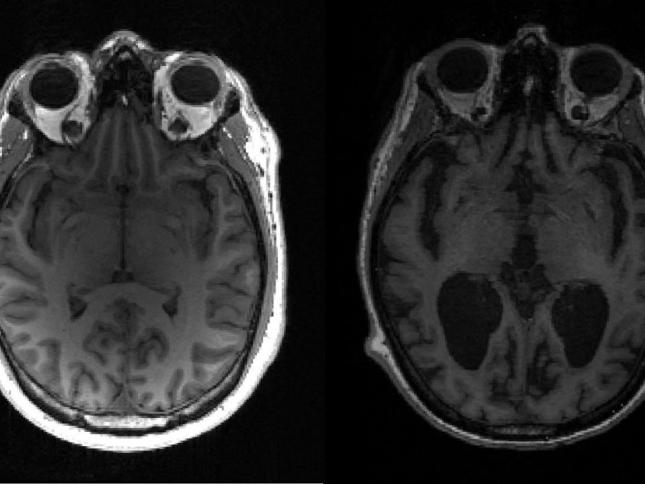

’مرتے وقت زندگی کے اہم واقعات دماغ کی سکرین پر چلنا شروع ہو جاتے ہیں‘

ایک بےحد اہم تحقیق سے پتہ چلتا ہے کہ مرتے وقت آخری سیکنڈوں میں انسان کے دماغ کے اندر اس کی زندگی کے اہم واقعات دہرائے جاتے ہیں۔